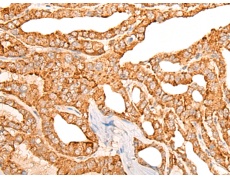

IHC positive control: |

Human thyroid cancer |

ELISA, IHC |